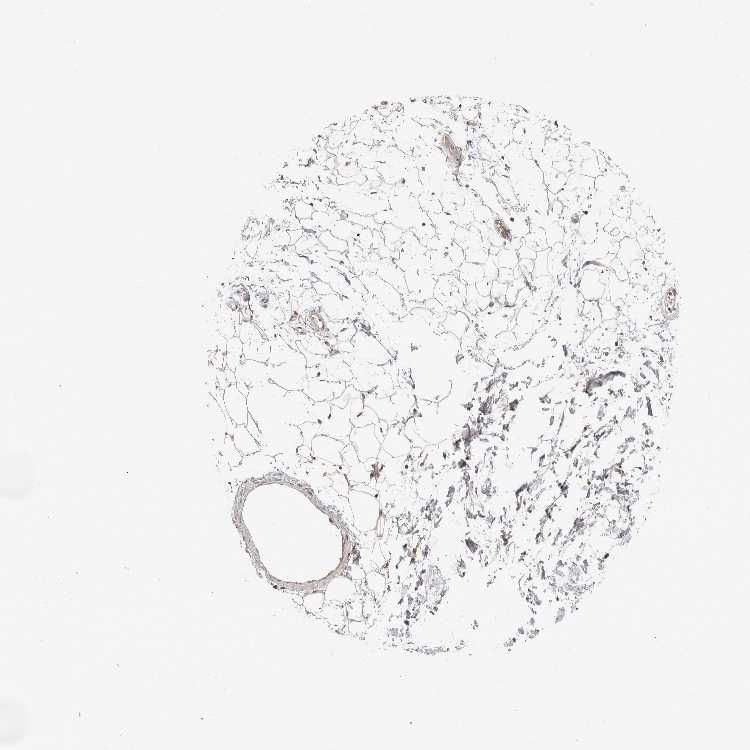

SOFT TISSUE 1 - Antibody stainingi

Antibody staining in the annotated cell types in the current human tissue is reported as not detected, low, medium, or high, based on conventional immunohistochemistry profiling in selected tissues. This score is based on the combination of the staining intensity and fraction of stained cells.

Each image is clickable and will lead to virtual microscopy that enables deeper exploration of all samples and also displays staining intensity scores, fraction scores and subcellular localization as well as patient and tissue information for each sample.

Antibody HPA026488Antibody HPA028425Antibody CAB011203

Chondrocytes Not detected--

Fibroblasts Not detectedNot detectedLow

Peripheral nerve Not detectedNot detectedNot detected

SOFT TISSUE 2 - Antibody stainingi